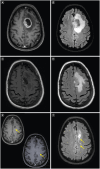

Patient's intracranial glioblastoma throughout the therapy course. (A) Preoperative axial T1 post-contrast brain MRI shows a left frontal heterogeneously enhancing mass. (B) Preoperative axial T2/FLAIR brain MRI shows surrounding vasogenic edema. (C) Postoperative axial T1 postcontrast brain MRI shows near total resection of the previously seen enhancing tumor. (D) Post-operative axial T2/FLAIR brain MRI shows persistent hyperintensity. (E) Radiation planning axial T1 post-contrast brain MRI shows interval development of contrast-enhancing lesions at the posterior margin of the resection cavity and posterior to the resection cavity (yellow arrows). (F) Radiation planning axial T2/FLAIR brain MRI shows hyperintensity associated with the new enhancing lesions. (G) Post-radiation axial T1 post-contrast brain MRI shows interval enlargement of the prior lesion posterior to the resection cavity. (H) Post-radiation T2/FLAIR axial brain MRI shows surrounding vasogenic edema. (I) Re-resection postoperative T1 postcontrast axial brain MRI shows near total resection of the prior enhancing mass. (J) Re-resection postoperative T2/FLAIR axial brain MRI shows improvement in the surrounding vasogenic edema. (K) Post 2 cycles of lomustine and 3 cycles of bevacizumab, T1 post-contrast axial brain MRI shows interval development of a contrast-enhancing mass. (L) Post 2 cycles of lomustine and 3 cycles of bevacizumab, T2/FLAIR axial brain MRI shows surrounding vasogenic edema. (M) Post 2 cycles of lomustine and 4 cycles of bevacizumab, T1 post-contrast axial brain MRI shows interval enlargement of the contrast-enhancing mass. (N) Post 2 cycles of lomustine and 4 cycles of bevacizumab, T2/FLAIR axial brain MRI shows surrounding vasogenic edema. (O) Post 10 days of lenvatinib, T1 post-contrast axial brain MRI shows an interval decrease in the previously seen contrast-enhancing mass. (P) Post 10 days of lenvatinib, T2/FLAIR axial brain MRI shows an interval decrease in the previously seen T2/FLAIR hyperintensity. (Q) Post 10 days of lenvatinib, DWI axial brain MRI shows associated abnormal signals with the aforementioned mass. (R) Post 10 days of lenvatinib, ADC axial brain MRI shows minimal ADC correlate along the lateral margin of the mass.